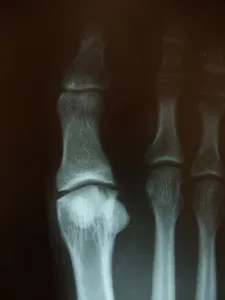

• X-rays are taken to evaluate the joint surface.

• If an x-ray is positive for an osteochondral lesion, then a CT scan may be necessary to help stage the lesion (I through IV) and evaluate the size of the lesion.